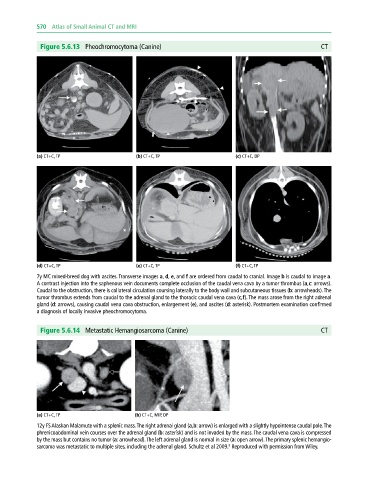

Figure 5.6.13 Pheochromocytoma (Canine) CT

(a) CT+C, TP (b) CT+C, TP (c) CT+C, DP

(d) CT+C, TP (e) CT+C, TP (f) CT+C, TP

7y MC mixed‐breed dog with ascites. Transverse images a, d, e, and f are ordered from caudal to cranial. Image b is caudal to image a.

A contrast injection into the saphenous vein documents complete occlusion of the caudal vena cava by a tumor thrombus (a,c: arrows).

Caudal to the obstruction, there is collateral circulation coursing laterally to the body wall and subcutaneous tissues (b: arrowheads). The

tumor thrombus extends from caudal to the adrenal gland to the thoracic caudal vena cava (c,f). The mass arose from the right adrenal

gland (d: arrows), causing caudal vena cava obstruction, enlargement (e), and ascites (d: asterisk). Postmortem examination confirmed

a diagnosis of locally invasive pheochromocytoma.

Figure 5.6.14 Metastatic Hemangiosarcoma (Canine) CT

(a) CT+C, TP (b) CT+C, MIP, DP

12y FS Alaskan Malamute with a splenic mass. The right adrenal gland (a,b: arrow) is enlarged with a slightly hypointense caudal pole. The

phrenicoabdominal vein courses over the adrenal gland (b: asterisk) and is not invaded by the mass. The caudal vena cava is compressed

by the mass but contains no tumor (a: arrowhead). The left adrenal gland is normal in size (a: open arrow). The primary splenic hemangio-

sarcoma was metastatic to multiple sites, including the adrenal gland. Schultz et al 2009. Reproduced with permission from Wiley.